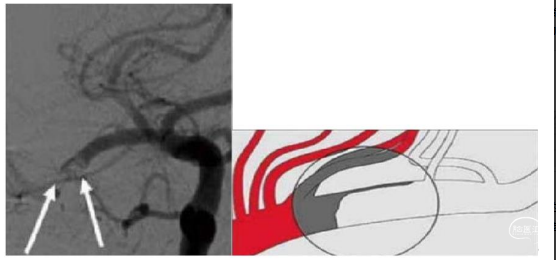

五、爪征征象

爪征血管末端造影剂存在半球形的充盈缺损,形似爪子的区域。爪征患者可能为房颤导致血栓栓塞,提示圆形或椭圆形的血栓形状,通过抽吸或支架取栓实现血管再通。

六、新月征

新月征类似爪征,是爪征的另一种表现。